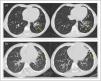

Foreign body aspiration was not suspected in either patient due to the lack of a choking episode, which resulted in delayed diagnosis and the development of bronchiectasis that persisted even five years after removal of the object (Fig. 3).